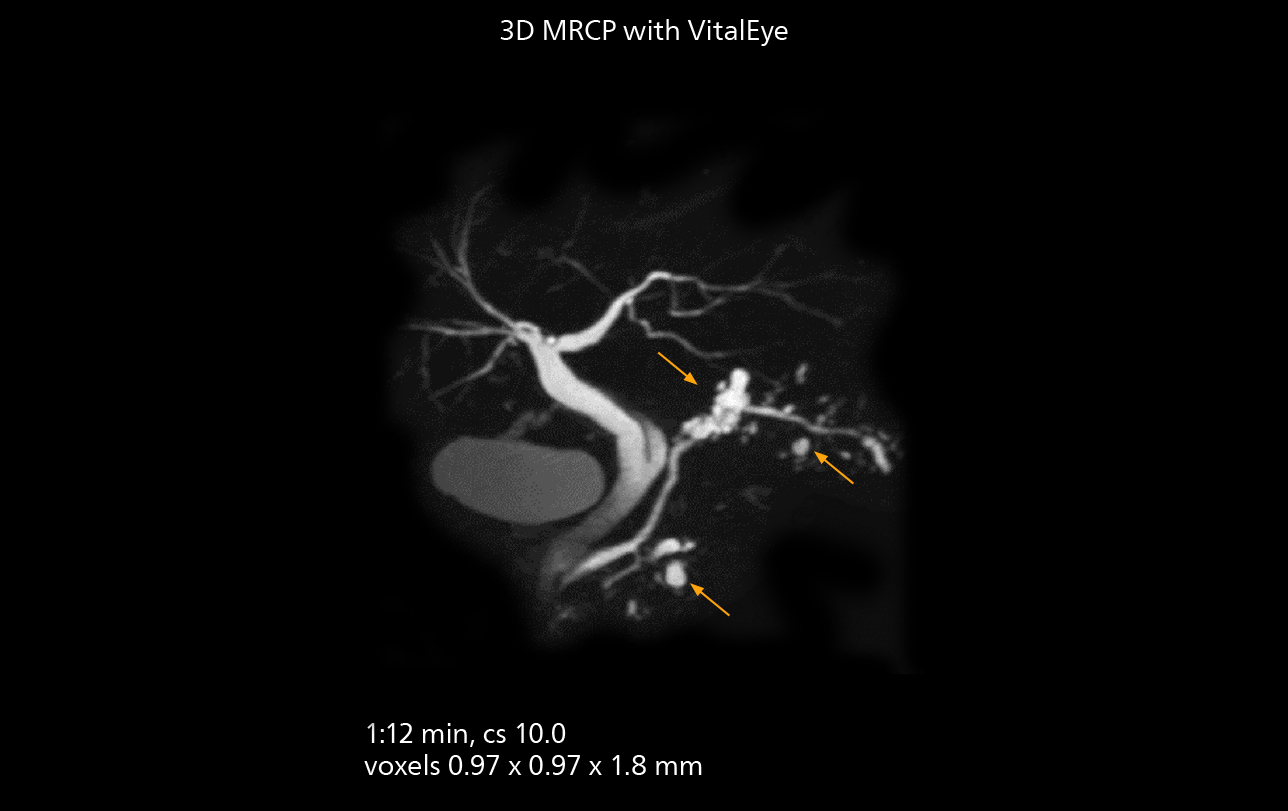

Workflow innovations streamline studies

SmartPath to Elition X comes with Smart Workflow technologies that support technologists and can save them time. VitalEye for touchless patient sensing is one example. “The implementation of VitalEye respiratory synchronization has had a significant impact,” says MR technologist Yoshihiro Otsu, Chief of the Radiological Department. “It not only improves workflow, but it also has increased the quality of examinations. Particularly for the large number of MRCP examinations performed in this hospital, VitalEye has increased the possibility to obtain sharp images with less blurring. Clinicians here really appreciate this improvement in MRCP image quality.” The VitalScreen on the scanner has helped reduce the risk of patient misidentification. “It allows patient information to be viewed in the magnet room when standing next to the patient,” he says. “And the automated patient centering in the magnet is very useful as well.” Apart from reducing stress for technologists, Smart Workflow helps improve respiratory synchronization and reduce examination stress for the patient.

VitalEye has increased the possibility of obtaining sharp images with less blurring. Clinicians here really appreciate this improvement in MRCP image quality.”

Yoshihiro Otsu

MRCP

With SmartPath to Elition X, the MRCP examinations at Sannodai Hospital benefit from VitalEye: respiratory synchronization is possible without respiratory belt positioning and image quality is excellent.

MRCP

With SmartPath to Elition X, the MRCP examinations at Sannodai Hospital benefit from VitalEye: respiratory synchronization is possible without respiratory belt positioning and image quality is excellent.